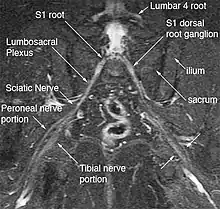

Magnetic resonance imaging (MRI) and magnetic resonance neurography (MRN) are the diagnostic procedures of choice for deep gluteal syndrome.[4][6][3] MRN provides additional information that MRI alone can't by visualizing structural properties of the sciatic nerve.[3] As an example of the diagnostic improvement of MRN, when MRI is used to assess piriformis muscle asymmetry, it has 46% sensitivity and 66% specificity for piriformis syndrome. When MRN is used and includes unilateral sciatic nerve hyperintensity at the sciatic notch, the sensitivity increases to 64% and the specificity increases to 93%.[3] MRN's advantage is in identifying anatomic nerve abnormalities by visualizing neural structures such as nerve diameter, nerve fascial edema, fascicular appearance, perifascicular and endoneural signal intensity.[5][6] Diffusion tensor imaging / Magnetic resonance tractography is expected to be another powerful clinical tool for diagnosis of deep gluteal syndrome because it can reveal additional physiological information about the nerves, but is still in the research phase.[6]